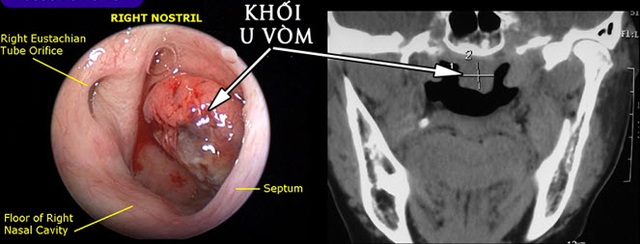

Theo BCSKII Đinh Viết Thanh, khoa Tai Mũi Họng, Bệnh viện tỉnh Quảng Trị, ông N.V.B đến khám tại phòng khám Tai Mũi Họng với lý do ù tai kéo dài và có hạch vùng góc hàm trái. Bệnh nhân được nội soi và phát hiện khối u chiếm toàn bộ vòm mũi họng sần sùi tăng sinh mạch máu. Xét nghiệm giải phẫu bệnh chẩn đoán ung thư vòm giai đoạn muộn.

Hình ảnh nội soi và cắt lớp vi tính khối u vòm họng.